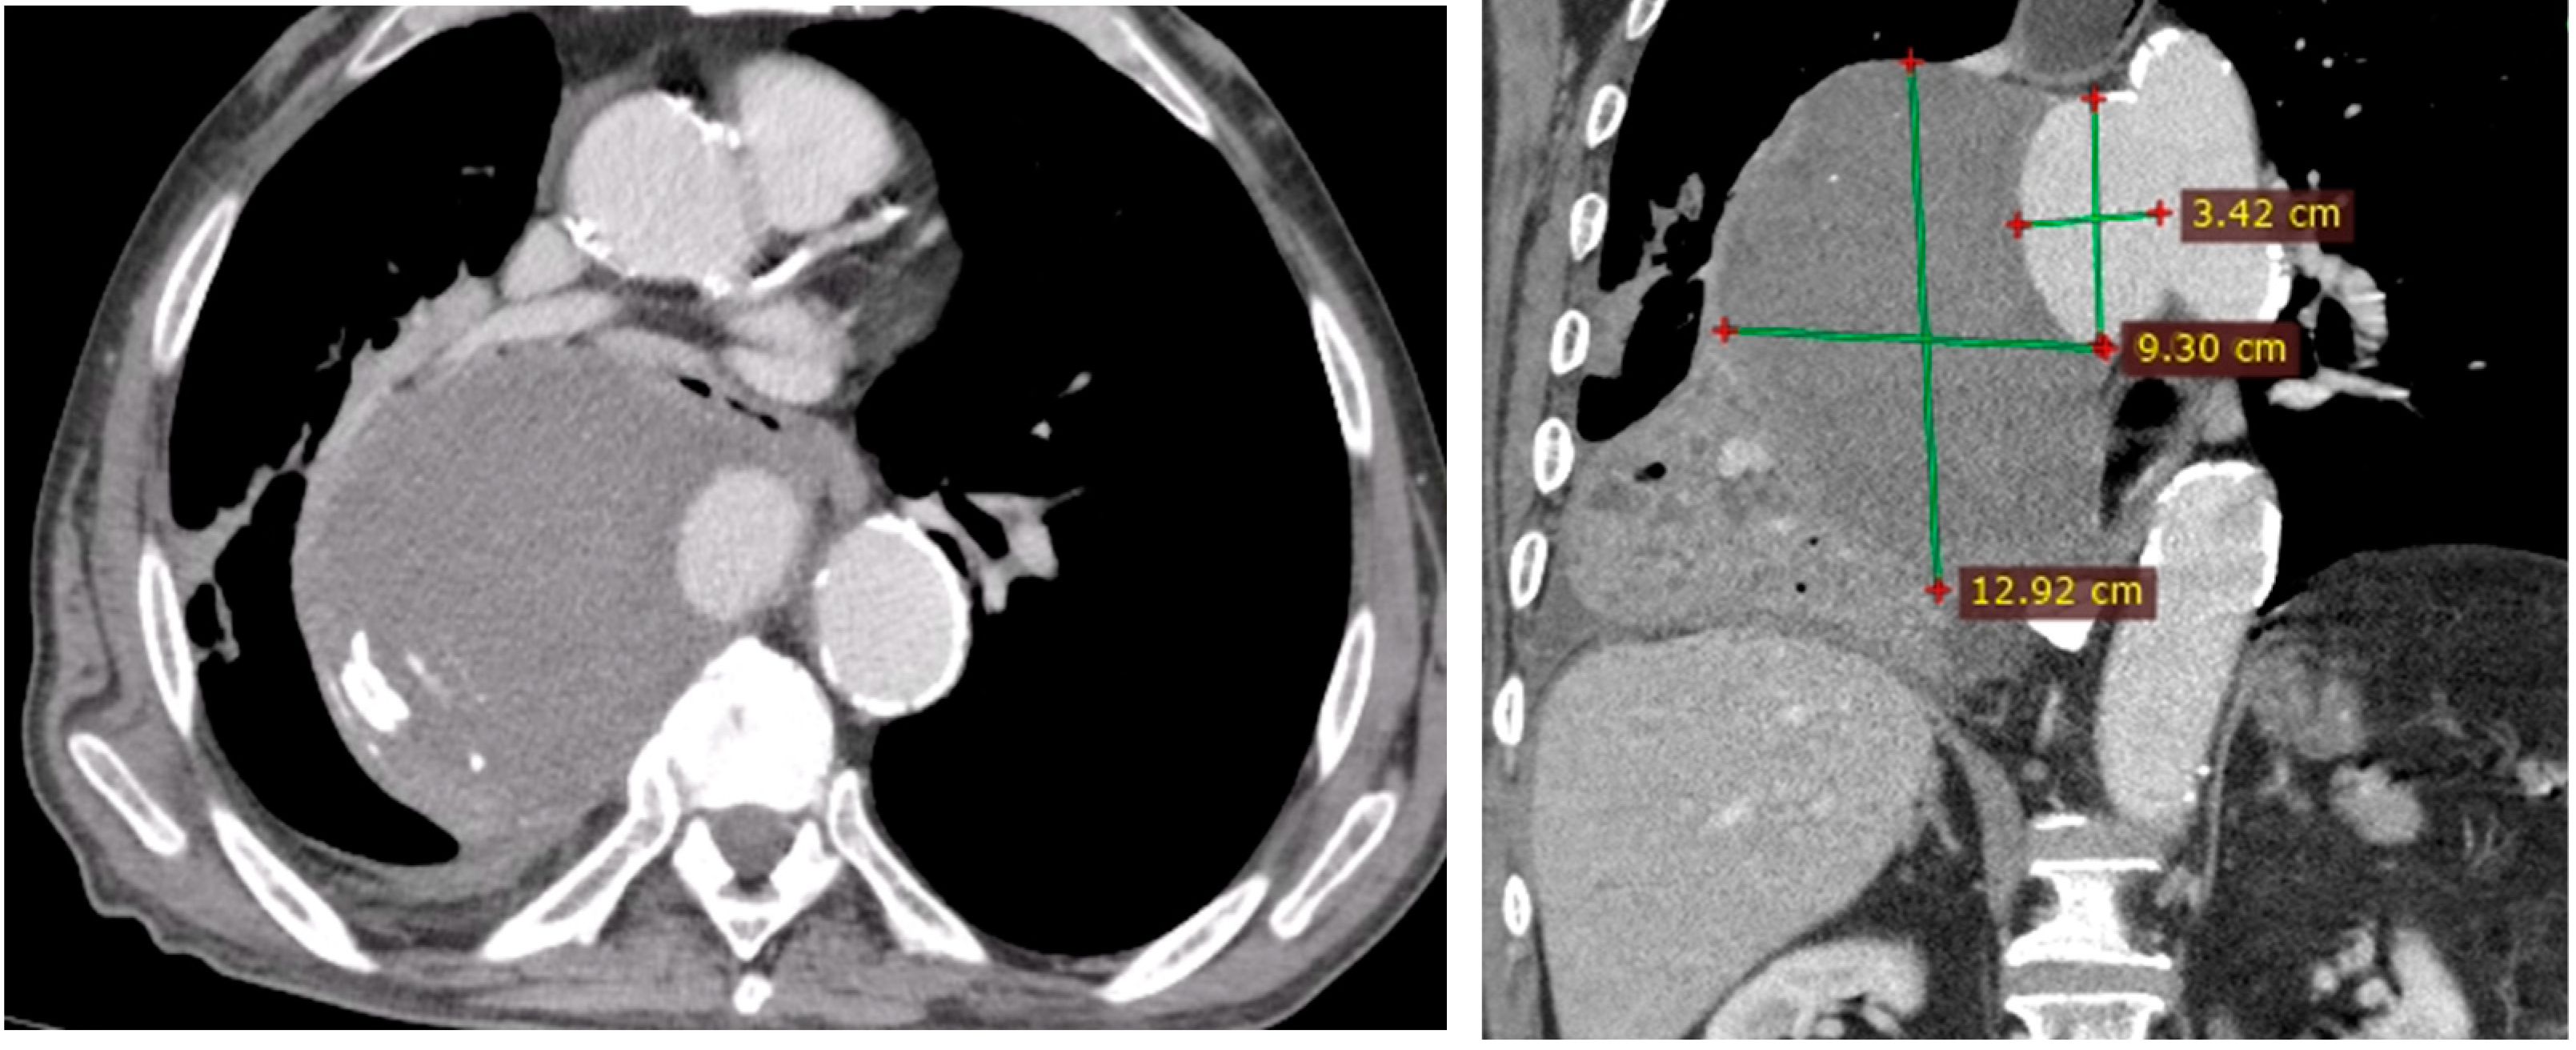

- Penetrating aortic ulcer ruptured: As seen in Figure 2, the thoracic angio-CT scan identified a penetrating ulcer within the aortic wall, particularly located in the isthmic region, measuring approximately 4.2 cm × 3.5 cm. This was a concealed source of significant concern, as it posed an imminent risk of catastrophic hemorrhage.

- Right pleural aortic false aneurysm (Figure 3): The most striking feature was the presence of an expansive false aneurysm within the right pleural cavity, measuring approximately 12.92 cm × 9.3 cm. The size and location of this pseudoaneurysm were unprecedented, introducing a challenge in terms of diagnosis and intervention.